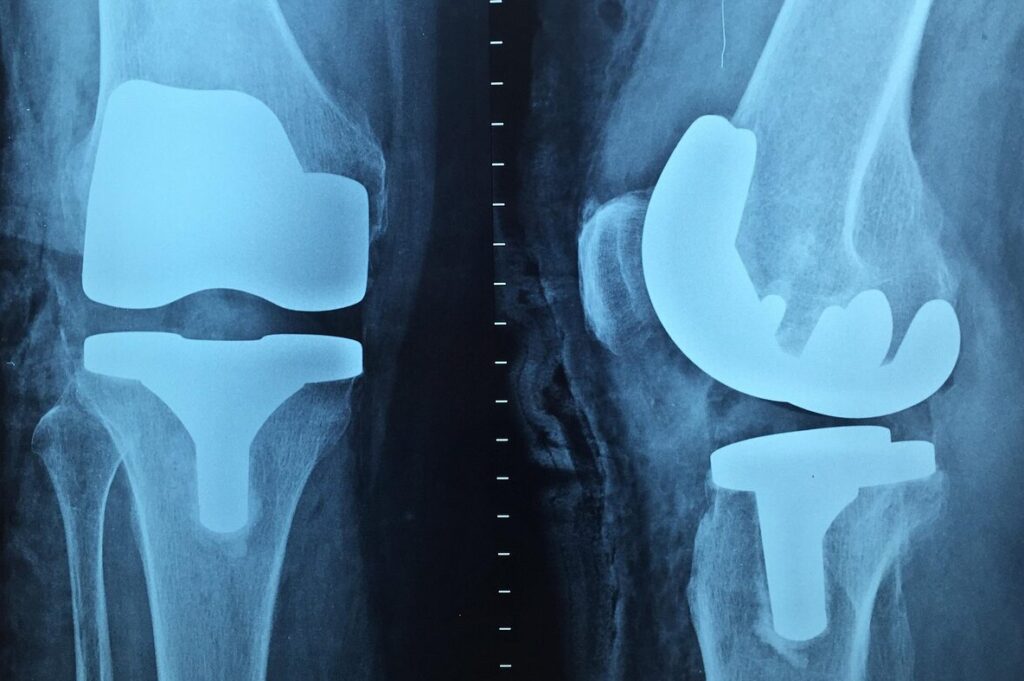

Een knieprothese (kunstknie) is één van de meest voorkomende orthopedische operaties in Nederland. Jaarlijks krijgen duizenden mensen een nieuwe knie om slijtage (artrose) of letsel te behandelen. Het succes van de operatie hangt sterk af van een goed revalidatietraject.